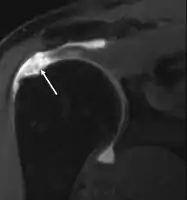

Diagnostic modalities, dependent on circumstances, include X-ray, MRI, MR arthrography, double-contrast arthrography, and ultrasound. Although MR arthrography is currently considered the gold standard, ultrasound may be most cost-effective.[31] Usually, a tear will be undetected by X-ray, although bone spurs, which can impinge upon the rotator cuff tendons, may be visible.[32] Such spurs suggest chronic severe rotator cuff disease. Double-contrast arthrography involves injecting contrast dye into the shoulder joint to detect leakage out of the injured rotator cuff[33] and its value is influenced by the experience of the operator. The most common diagnostic tool is magnetic resonance imaging (MRI), which can sometimes indicate the size of the tear, as well as its location within the tendon. Furthermore, MRI enables the detection or exclusion of complete rotator cuff tears with reasonable accuracy and is also suitable to diagnose other pathologies of the shoulder joint.[34]

MRI

Magnetic resonance imaging (MRI) and ultrasound[42] are comparable in efficacy and helpful in diagnosis although both have a false positive rate of 15 - 20%.[43] MRI can reliably detect most full-thickness tears although very small pinpoint tears may be missed. In such situations, an MRI combined with an injection of contrast material, an MR-arthrogram, may help to confirm the diagnosis. It should be realized that a normal MRI cannot fully rule out a small tear (a false negative) while partial-thickness tears are not as reliably detected.[44] While MRI is sensitive in identifying tendon degeneration (tendinopathy), it may not reliably distinguish between a degenerative tendon and a partially torn tendon. Again, magnetic resonance arthrography can improve the differentiation.[44] An overall sensitivity of 91% (9% false negative rate) has been reported indicating that magnetic resonance arthrography is reliable in the detection of partial-thickness rotator cuff tears.[44] However, its routine use is not advised, since it involves entering the joint with a needle with potential risk of infection. Consequently, the test is reserved for cases in which the diagnosis remains unclear.